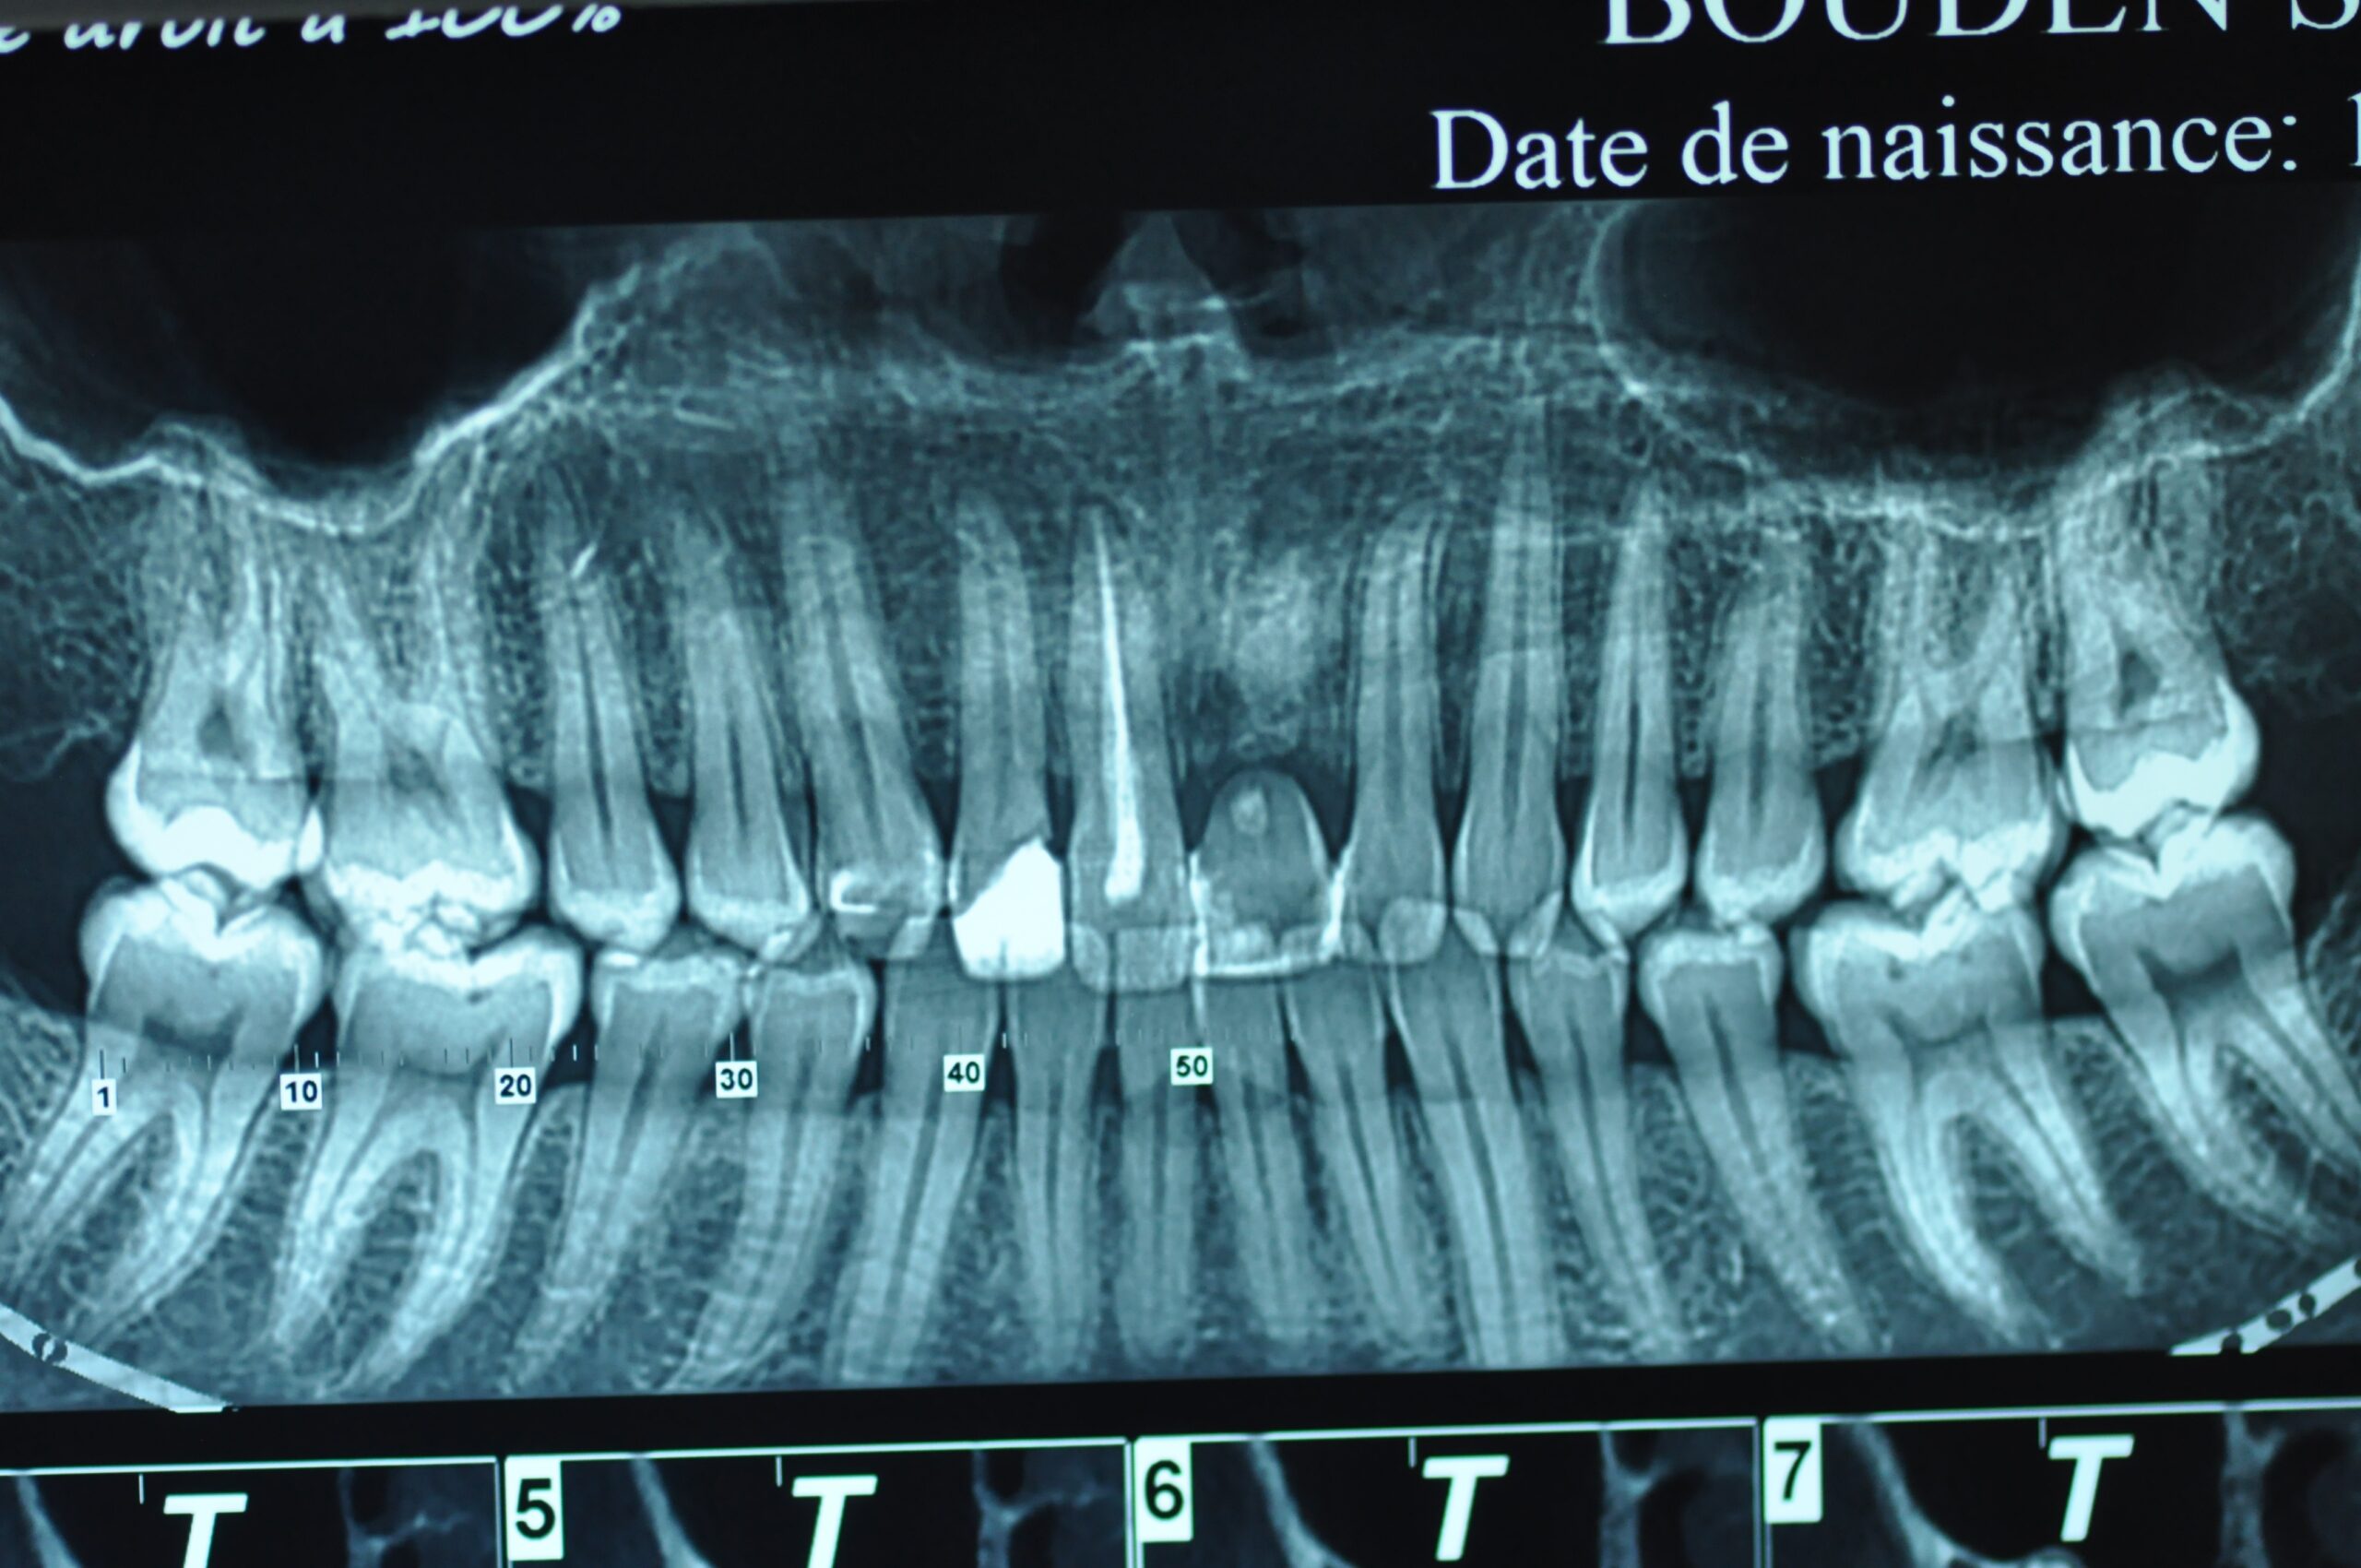

Un implant dentaire est une racine artificielle en titane qui remplace la racine manquante d’une dent naturelle. Il est placé dans la mâchoire inférieure ou supérieure pour remplacer une ou plusieurs dents. Après la période de cicatrisation osseuse, la couronne est fixée au-dessus de l’implant.

La pose d’un implant dentaire s’effectue en plusieurs étapes étalées sur quatre à neuf mois, et en règle générale, de la façon suivante :

Après une étude approfondie de vos antécédents dentaires et médicaux, le dentiste détermine si les implants dentaires sont indiqués dans votre cas. Il examine ce qui doit être fait, se prépare et vous explique en plan de traitement à venir.